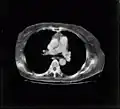

El TAC mejora el contraste de la radiología convencional, tal y como se ve en las siguientes imágenes.

La tomografía computarizada (TC), denominada en sus comienzos como TAC (Tomografía Axial Computarizada), es una técnica de imágenes digitales que ha tenido un gran impacto en el desarrollo de la medicina actual. Se basa en el uso de un haz de rayos X muy colimado, donde la radiación trasmitida a través de un objeto —en medicina, el paciente recostado en una mesa radiológica— es medida por un conjunto de detectores ubicados en oposición a la fuente de rayos X. Luego de múltiples mediciones realizadas alrededor del objeto, la respuesta eléctrica del set de detectores es enviada a un ordenador, el que mediante algoritmos computacionales (como por ejemplo, el algoritmo de retroproyección filtrada), es capaz de construir una imagen seccional del objeto utilizando la data medida y desplegarla finalmente sobre un monitor.

Esta imagen obtenida en TC es capaz de evidenciar las diferencias en las características de atenuación de las estructuras contenidas al interior de los objetos estudiados. Estas estructuras son visualizadas en el monitor con base en tonalidades de grises, las que se relacionan con un valor numérico denominado Unidad Hounsfield, asignado a cada pixel de la imagen. Este valor es calculado a partir del coeficiente de atenuación de cada material contenido en el objeto, comparado con el coeficiente del agua, usado como material de referencia. Esto mejora enormemente la resolución de contraste de la TC en comparación con la radiografía simple y la tomografía lineal. Además, mediante filtros de convolución aplicados durante el proceso de construcción de la imagen, se puede mejorar, por ejemplo, la definición de los bordes de las estructuras o reducir la presencia de ruido en las imágenes. El posterior manejo de ancho y nivel de ventana permite manipular el despliegue final de las imágenes para poner énfasis en las estructuras que se quiere visualizar de acuerdo al diagnóstico que se busca.

-

Imagen de corte de tomografía computarizada de pulmones con procesamiento para realce de bordes. -

Imagen de corte de tomografía computarizada de ambos pulmones sin procesamiento.